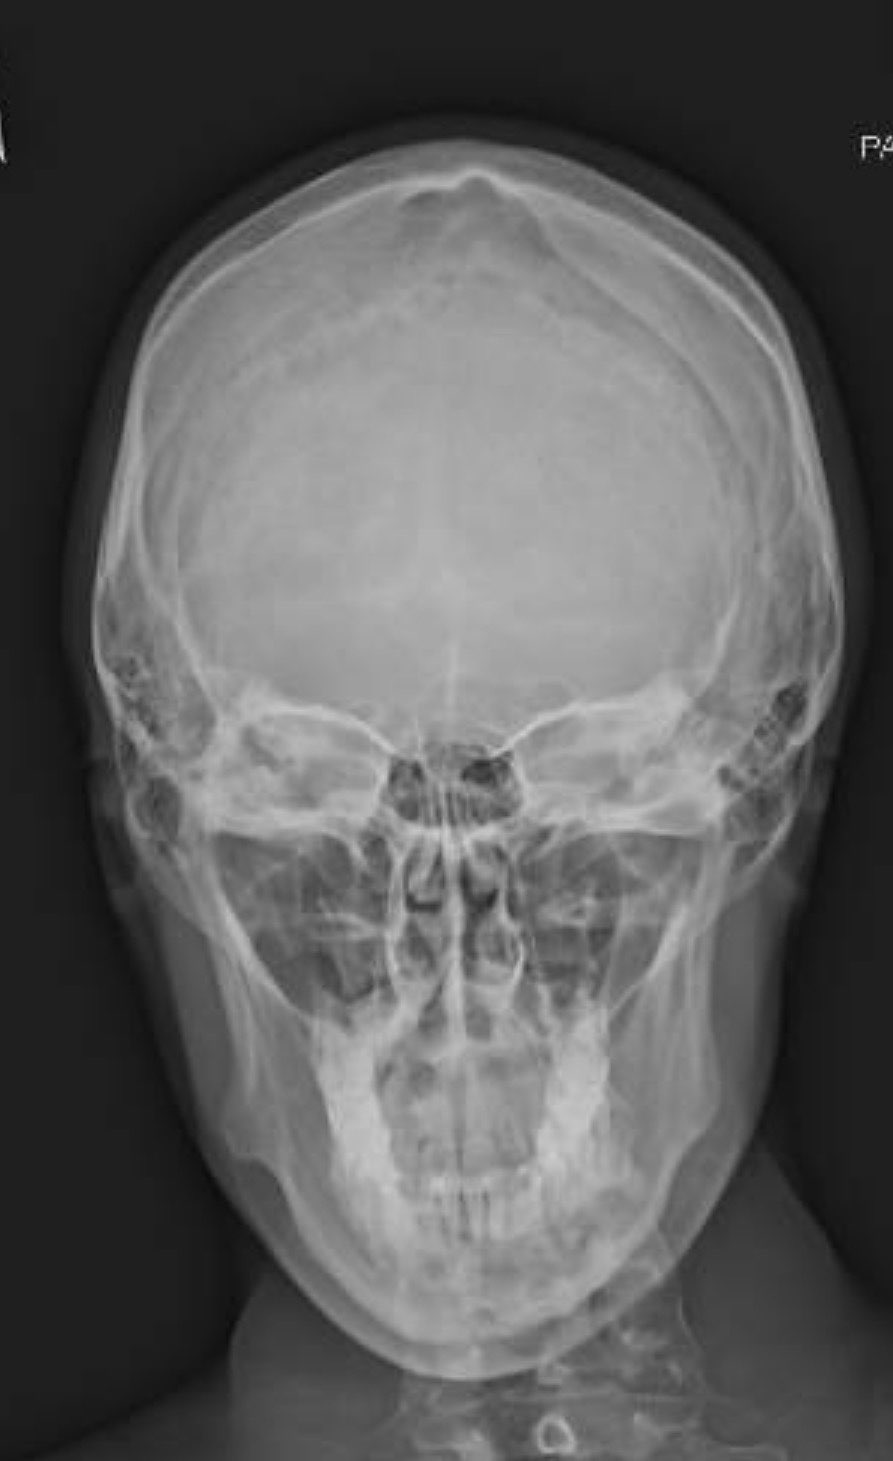

I have a borderline short face as you can see by my scans.

I have a long ramus and well rotated jaw, which I think fits the criteria, although I have a class 1 dental occlusion, we’re going to decompensate my teeth as much as possible, so I can get a bigger movement.

Do you think a small bit of downgrafting is necessary? I’m also gonna add height and width to my chin with custom genio.

My surgeon is gonna do roughly a 12mm BSSO and 5mm Lefort 1. Haven’t decided genio movements yet.

Also when I look at my CT scan and skull, it looks like I have asymmetry of the chin, this also appears to be the case when I look at my face too, here is the soft tissue scan of my face IMG 0754

It’s also worth mentioning that I used to have a cross bite, before orthodontics, is this fixeable?

Also when I look at my CT scan and skull, it looks like I have asymmetry of the chin, this also appears to be the case when I look at my face too, here is the soft tissue scan of my faceView attachment 4403692

I mean i dont see the assymetry, and assymetry is not 1 to 1 with bone. You could fix the bone assymetry but it would still look equally assymetric because soft tissue is formed that way. Bringing the lower jaw forward can expose new assymetries aswell. One of the downsides